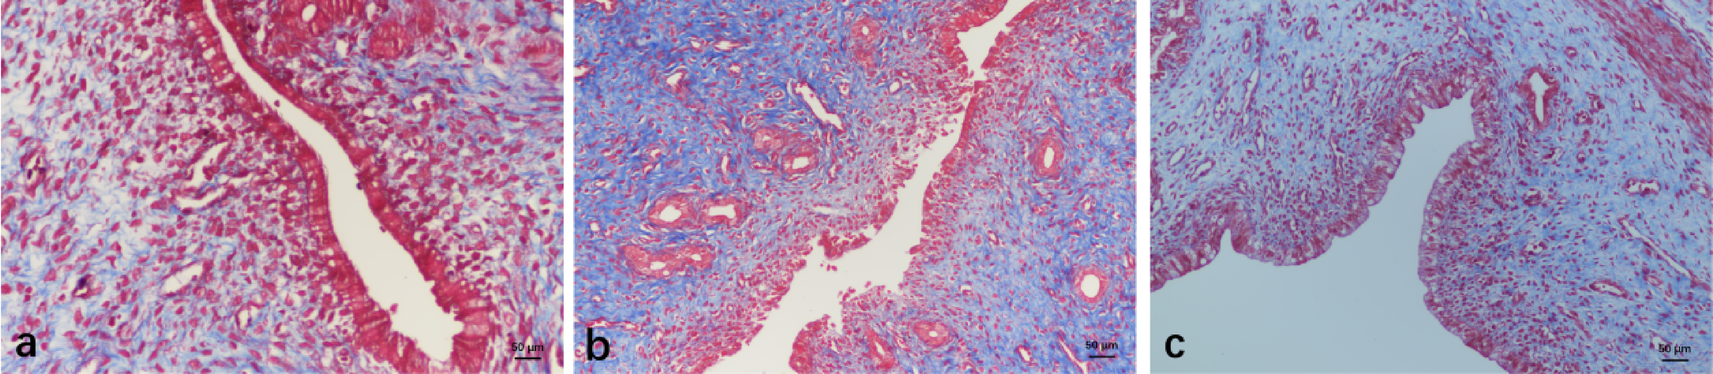

Masson Staining of Endometrial Samples. Endometrium of the normal group (a), model group (b) and the UC-MSCs group (c). All images are captured at a magnification of ×400. Scale bar: 50 μm.